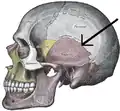

![]() Side view of the cranium. Squamosal suture highlighted. | |

The squamosal suture, or squamous suture, arches backward from the pterion and connects the temporal squama with the lower border of the parietal bone: this suture is continuous behind with the short, nearly horizontal parietomastoid suture, which unites the mastoid process of the temporal with the region of the mastoid angle of the parietal bone. The term parietotemporal suture may refer to both of these sutures or exclusively to the parietomastoid suture and its use is, therefore, best avoided.

Side view of the skull. Squamosal suture indicated by the black arrows.